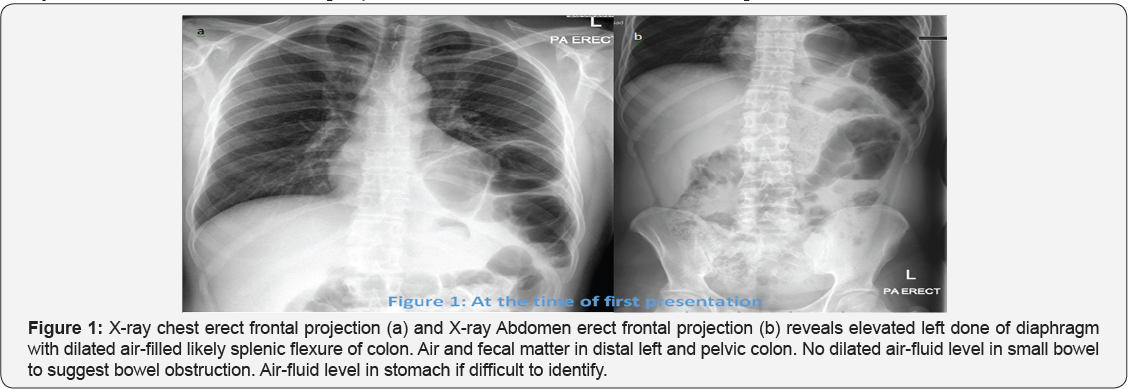

X-ray Chest and Abdomen erect projection recommended at time of first presentation

Impression of Figure 1: Above described findings representing differential diagnosis of left diaphragmatic eventration or left diaphragmatic hernia.